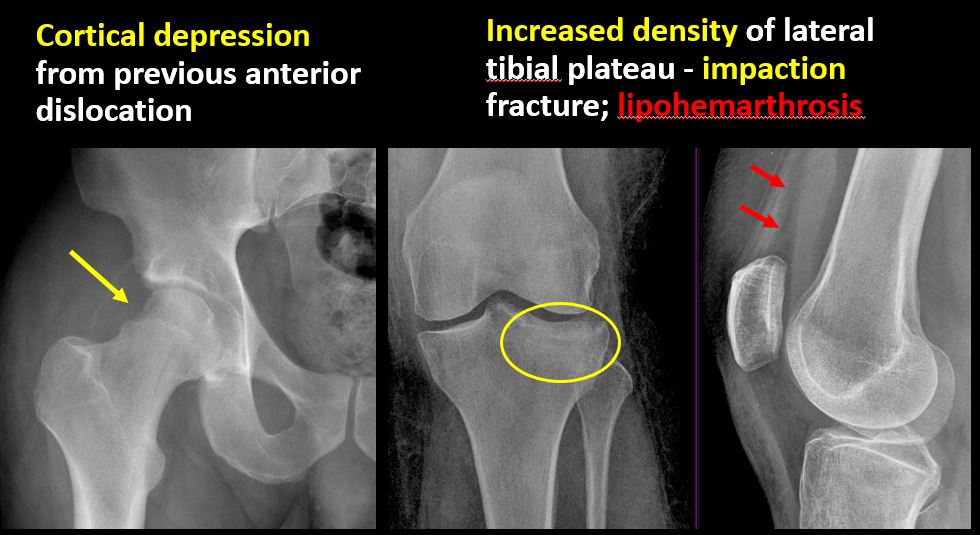

33 yo male s/p MVA with left knee pain.Exam

There is linear or irregular lucency, or increased density, cortical depression, flattening, or collapse with or without cortical disruption or thickening, which may be from a compression or impaction fracture, stress or insufficiency fracture, osteonecrosis, or other fracture. |

Yes | NA |

There is an impaction fracture of the medial posterior tibial plateau with a lipohemarthrosis. There is also an avulsion fracture of the lateral femoral epicondyle.

Call the ED physician with the results of the tibial plateau fracture. Recommend CT scan for further evaluation.